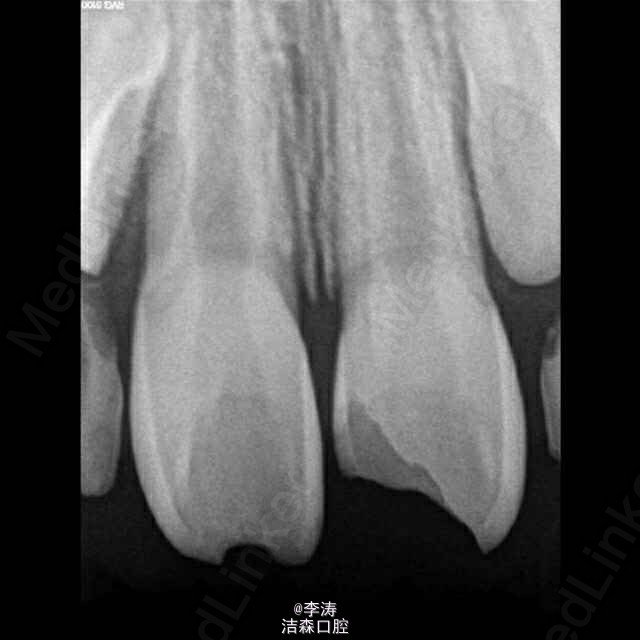

一7岁男孩上前牙外伤1小时就诊,检查,21牙牙冠大面积缺损未露髓,11牙牙釉质小部分缺损,牙龈红肿出血,未及明显松动,52,62牙未脱落,x线片未见明显根折,11牙可见根尖暗影,两牙根管口均粗大。 调颌后建议患者观察两周,若无牙髓症状,牙髓活力正常,可直接充填缺损。若出现牙髓症状,或者牙髓活力丧失,行根尖诱导成形术。 思考,此病例受伤牙未刚萌出恒牙,若牙髓失去活力,髓腔如此大,即使诱导成形成功将来能承担打桩做冠发挥咀嚼的功能么? 此病例两侧乳牙均未脱落,如果前牙有II~III度松动,怎么固定???用乳牙结扎应该不可行吧?